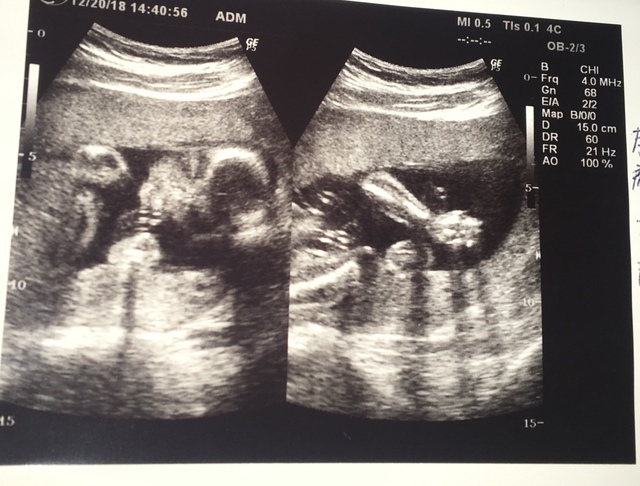

23週5日(23w5d・男の子)|とみとみ さん(29歳)

エコー写真撮影時のエピソード:

初めてエコー写真を見た時、このマメのようなものが人間になるの?と不思議な気持ちになりました。主人もこれ?と実感がわかない様子でしたが、月日が経つにつれて人間らしい姿になってくことに感動!

家族にも毎回エコー写真を送り成長を見てもらっていますが、すごーい、神秘だよねと毎回みんなで感動しています。